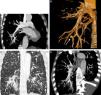

(A) Coronal maximum intensity projection (MIP) CT reconstruction, showing a Rasmussen's aneurysm (arrow) on a subsegmentary branch of the right lower lobe artery. (B) CT volumetric reconstruction (3D or volume rendering) confirming Rasmussen's aneurysm (arrow). (C) Coronal MIP CT reconstruction (pulmonary parenchyma window) showing signs of lung hemorrhage (asterisk) and bilateral residual infectious parenchymal opacities (arrows). (D) Coronal oblique MIP CT reconstruction after embolization showing embolization material (coil) occluding the Rasmussen's aneurysm (arrow).

We report the case of a 55-year-old man with advanced human immunodeficiency virus infection (stage C3), smoker and former intravenous drug user, who presented at our hospital with life-threatening hemoptysis, hypotension and tachycardia. In addition to emphysema phenotype chronic obstructive lung disease and hepatitis C-related liver cirrhosis, he had had multiple lung infections caused by unusual pathogens (Pneumocystis jirovecii, non-tuberculous mycobacteria, semi-invasive aspergillosis, etc.) that were treated, although treatment adherence was poor. A chest computed tomography (CT) angiography was performed, showing an aneurysm 1cm in diameter in the subsegmentary pulmonary artery of the right lower lobe (Fig. 1) and signs of ipsilateral pulmonary hemorrhage (Fig. 1C), associated with a Rasmussen's aneurysm. In view of the patient's hemodynamic instability, an angiogram with selective embolization of the aneurysm was performed, achieving complete occlusion of the lesion (Fig. 1D) and immediate resolution of hemoptysis. No dilation of the bronchial arteries or extravasation of contrast medium from these vessels was observed.